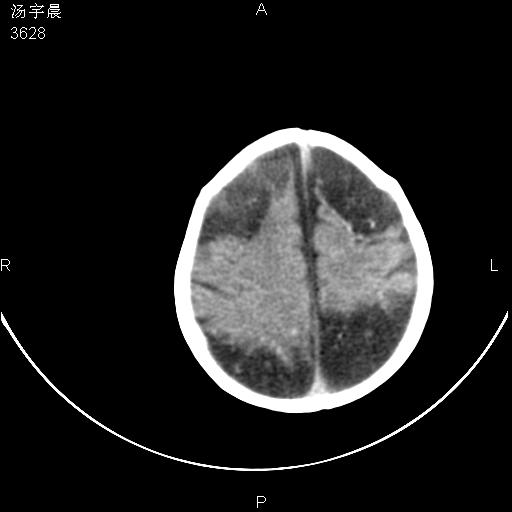

早产儿,现两月大,2月份在某医院诊断病毒性脑炎并治疗,mri报右颞部脑白质片状长t2信号,脑白质模糊。其他不详,现家属要求ct复查 。

双侧大脑半球大片状低密度,无明显占位表现, 符合病毒性脑炎。

小儿病毒性脑炎ct表现缺乏特异性,但其定位分布有一定特异性,单纯疱疹病毒性脑炎ct表现以颢叶病变为主,同时可累及其他脑区或伴出血,乙型脑炎表现为基底及丘脑的病变,流行性腮腺病毒性脑炎则ct表现可正常,故ct检查对病毒性脑炎的定性有重要的价值。 本例支持:病毒性脑炎的后遗改变!